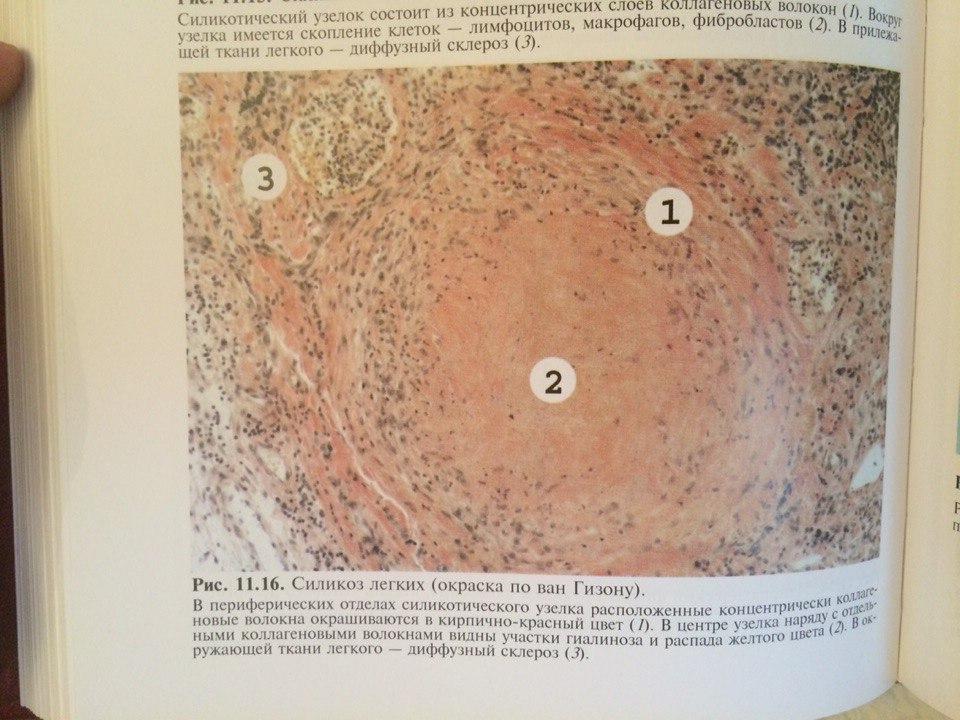

Карнификация Легкого: Микропрепараты и Диагностика

Раздел: Калейдоскоп образов